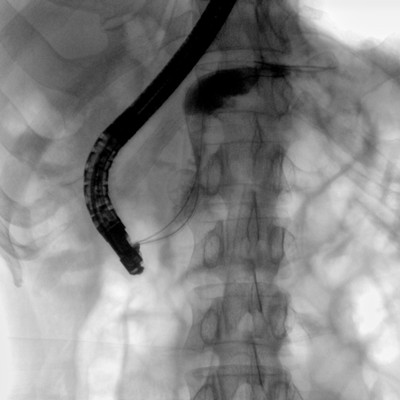

消化内科: ERCP、PTCD、肝脏介入(TACE、灌注)、食管支架等。